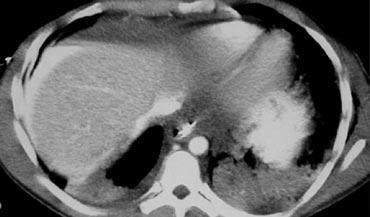

Trước tiên hãy quan sát các hình ảnh bên trái của bệnh nhân bị chấn thương gan.

Các dấu hiệu bao gồm:

- Mất tưới máu hoàn toàn thùy gan phải.

- Vùng ngấm thuốc cản quang (contrast blush) trong nhu mô gan, đồng thời lan ra ngoài bờ bên của gan.

- Tràn máu ổ bụng (Hemoperitoneum).

- Một vùng ngấm thuốc cản quang thứ hai ở mức thấp hơn.